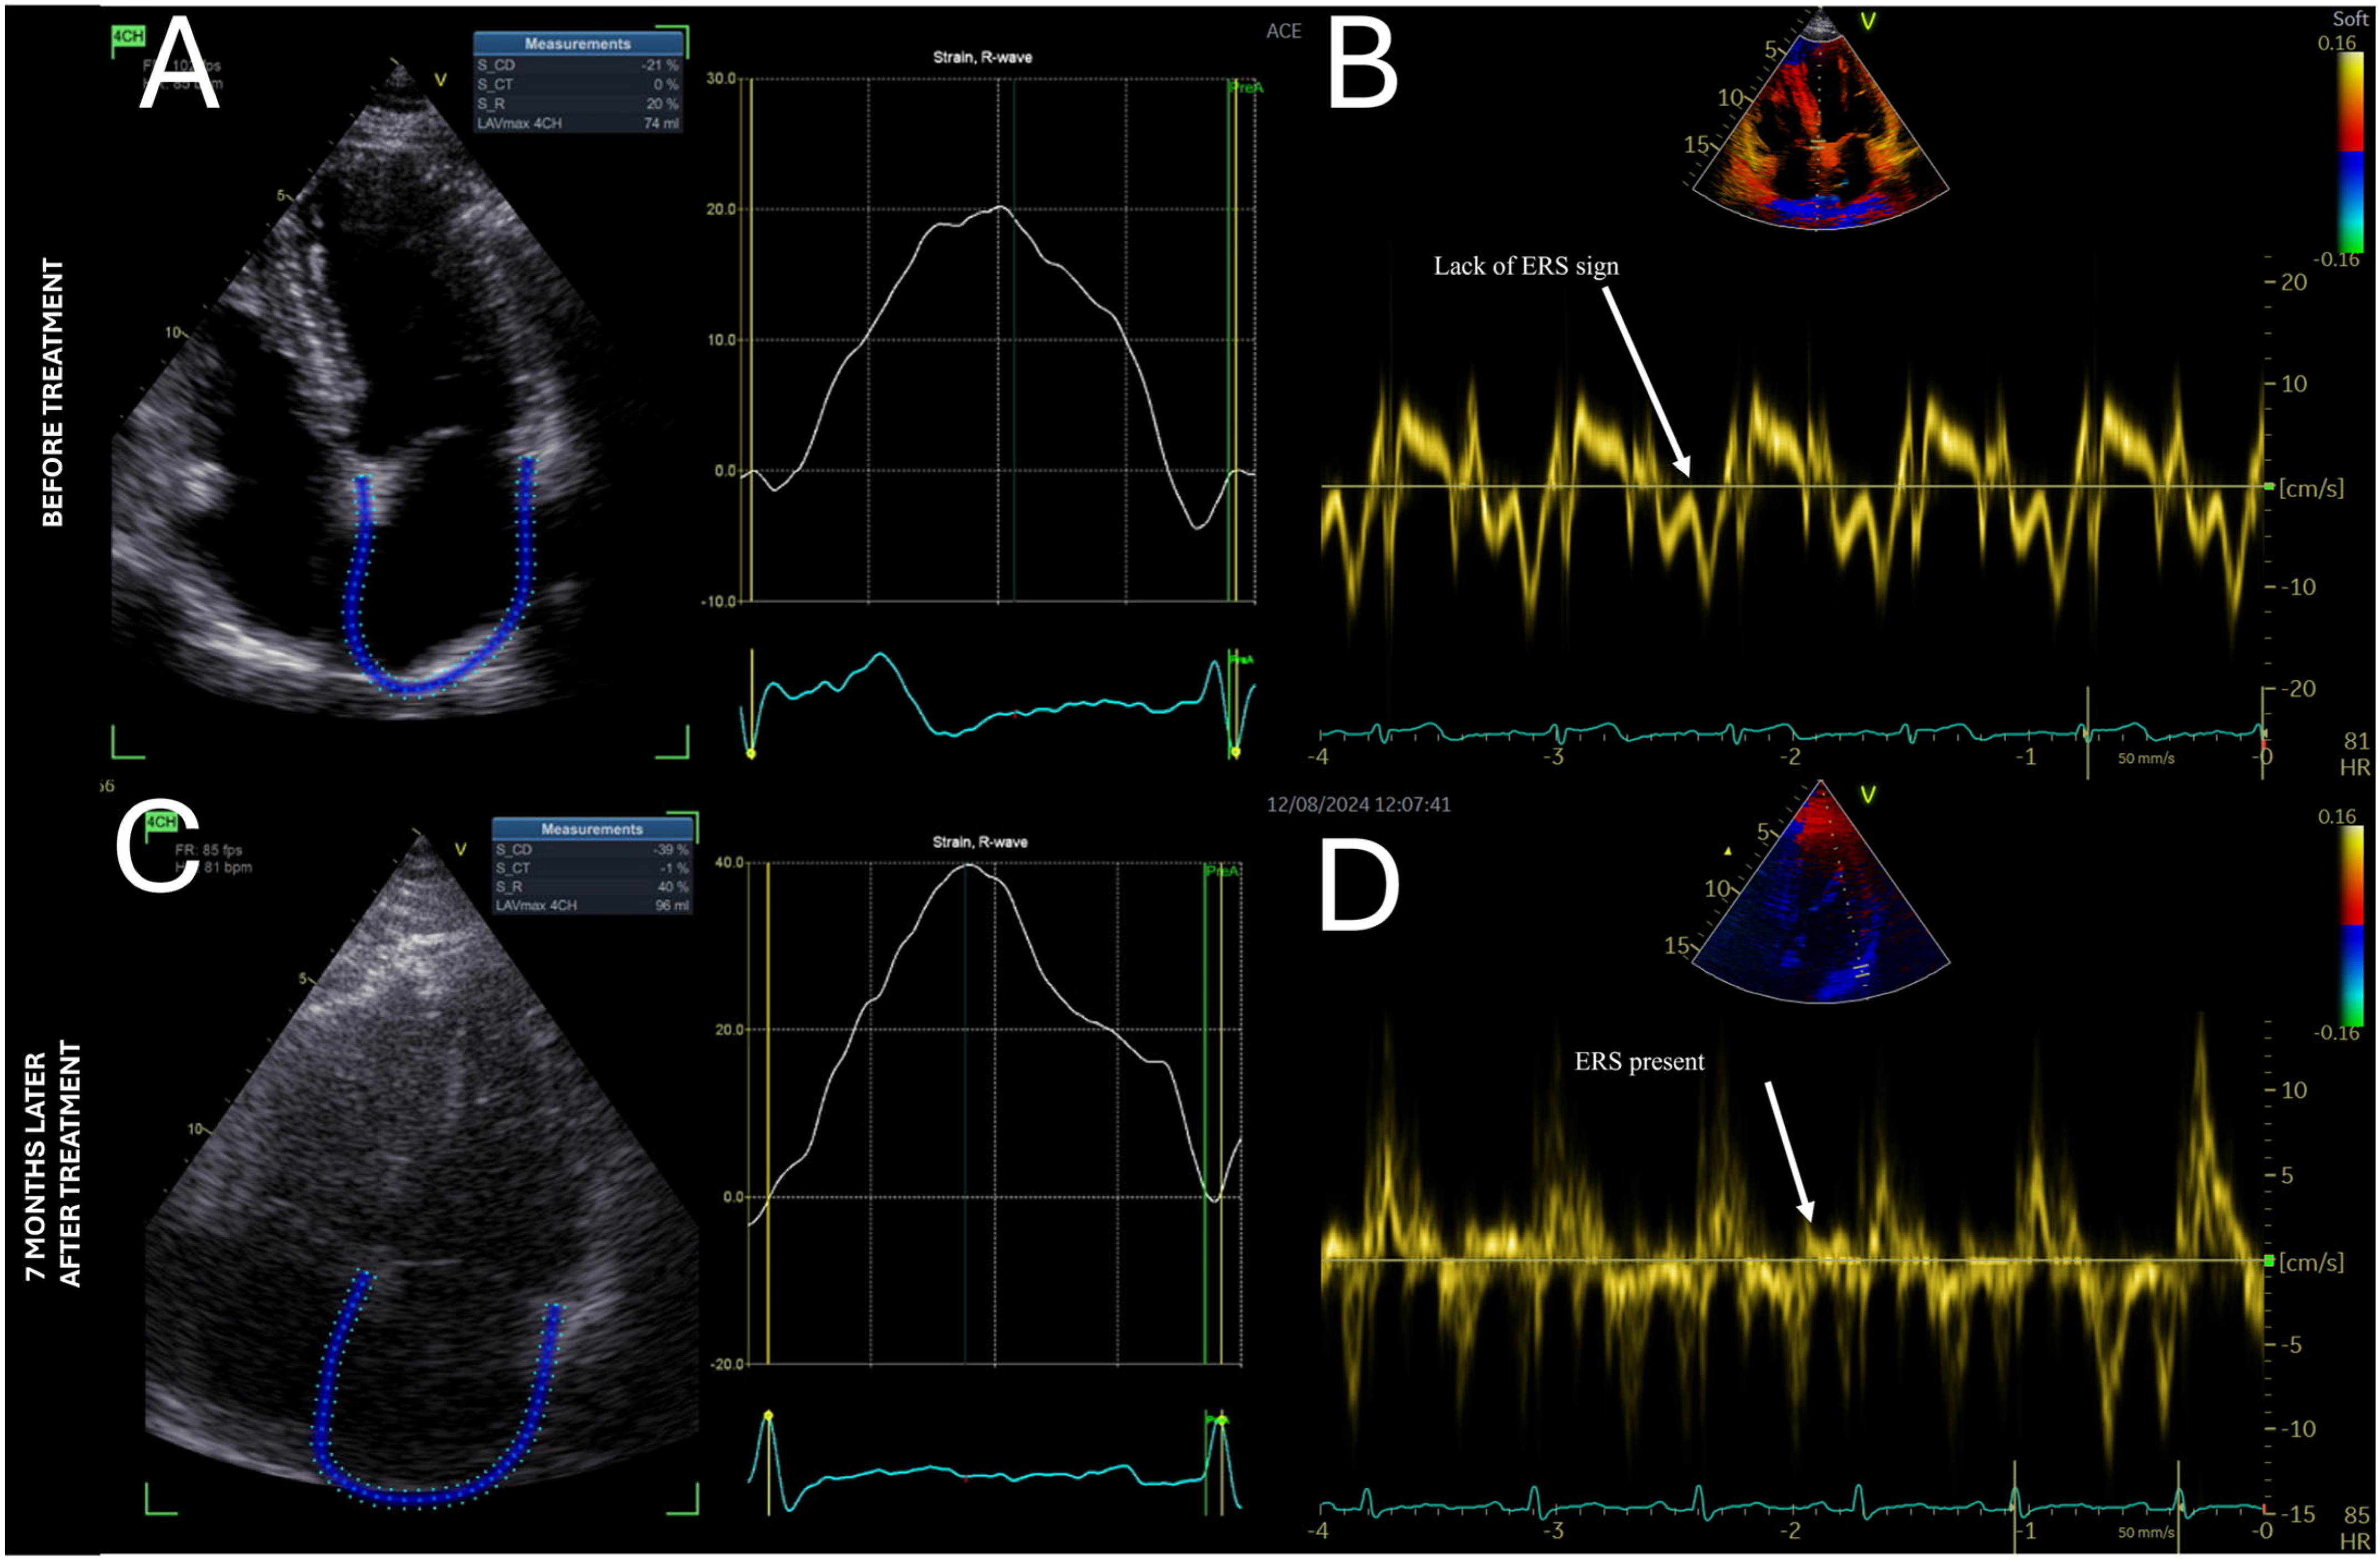

4. Case Report